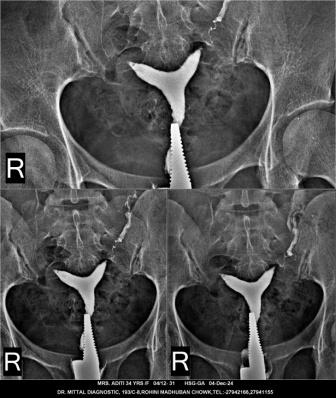

HSG TEST AVAILABLE IN DR MITTAL DIAGNOSTIC CENTRE SECTOR- 8 ROHINI DELHI 110085 Hysterosalpingogram (HSG) is an X-ray procedure that examines the uterus and fallopian tubes to check for blockages, abnormalities, or other issues.